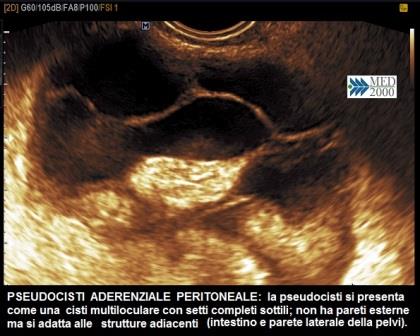

Inoltre nella fase cronica la vascolarizzazione della parete tubarica è modesta e non intensa come nelle forme acute. Può a volte coesistere un versamento pelvico in genere sotto forma di cisti da inclusione peritoneale (cisti anecogena con sottili setti incompleti, localizzata nel Douglas, che non avendo pareti esterne proprie mostra una morfologia che si adatta alla parete pelvica laterale ed all'intestino).